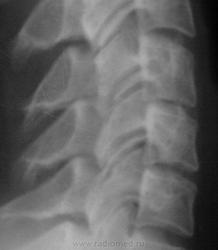

Не люблю молодым в заключениях писать всякие ...озы. В данном случае - женщина 25 лет. Мне кажеться, или на самом деле с дисками С4-С5-С6 не все в порядке? Если да, то какие костные компоненты подтверждают остеохондроз? Или просто - хондроз?

Явное снижение высоты С4-С5-С6 дисков. Да и микроретролистез С4 имеется.

дискоз С4-С6

Здравствуйте, я считаю, что явные признаки остеохондроза прослеживаются в сегменте С4-С6, вероятнее также при исследовании с функциональными пробами будут видны явления нестабильности в сегменте С4-С5.

по канону высота мпд нарастает в каудальном направлении, а здесь?

задний контур тел лестницеобразный.

"умеренный" остеохондроз С4-С6 сегмента. На мрт очень вероятно будет дорзальное выбухание дисков С4-С5, С5-С6.

с моей точки зрения, С4-С5 и С5-С6 сужены. совсем немного, но сужены.

смещение тела позвонка есть, но незначительное. нестабильностью считается - больше 2 мм, а тут кажется 1 мм....

По поводу снимков от Игоря Ивановича: незначительное снижение высоты С4-5-6 диска с малым ретролистезом С4. Этим бы и ограничилась, без заключения.